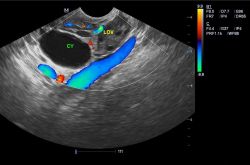

右側卵巢囊腫是什么 專家告訴您根治的方法

右側卵巢囊腫是什么 專家告訴您根治的方法,卵巢囊腫是女性生殖器官的一種常見的良性腫瘤,但因此病癥初期表現(xiàn)

卵巢囊腫是什么原因引起的 揭密卵巢囊腫的危害

卵巢囊腫是什么原因引起的 揭密卵巢囊腫的危害,卵巢囊腫時下已成為當代女性常見的一種疾病,而在平時女性對于

卵巢腫瘤的病因是什么 揭卵巢腫瘤的早期癥狀

卵巢腫瘤的病因是什么 揭卵巢腫瘤的早期癥狀,卵巢腫瘤是目前較為常見的一種婦科疾病,這種疾病的發(fā)生從幼兒到